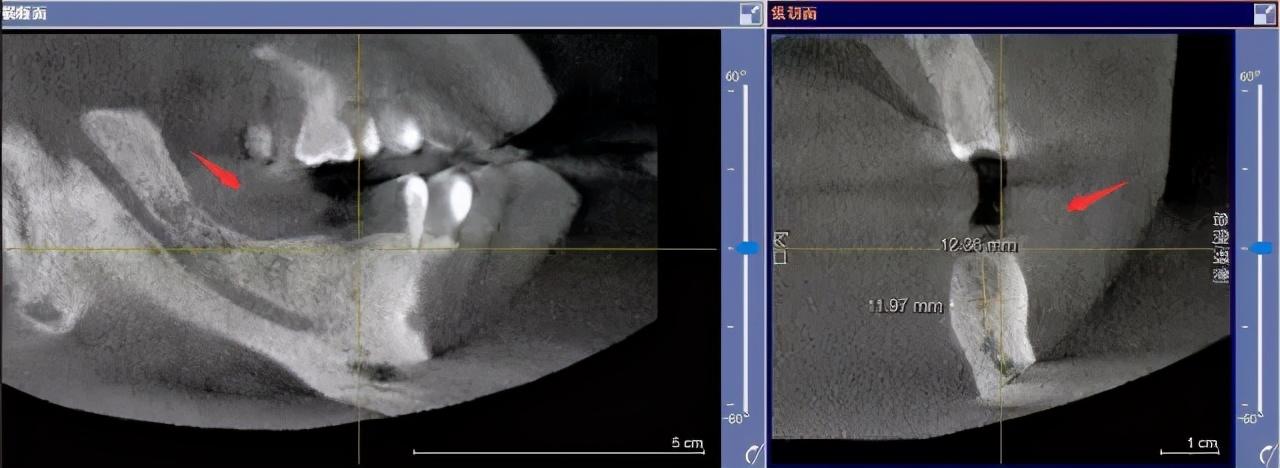

注明:此數(shù)據(jù)僅作模擬,不是確切種植數(shù)據(jù)。

如果僅靠雙眼大致估測口內(nèi)數(shù)據(jù),是無法得到的高度、寬度的,也無法確認(rèn)骨頭吸收多少,是否需要植入骨粉。

對后期手術(shù)有一定的影響。

通過全景片可以“解剖”牙齒測量,適宜的種植角度也可確定,健康有保障。